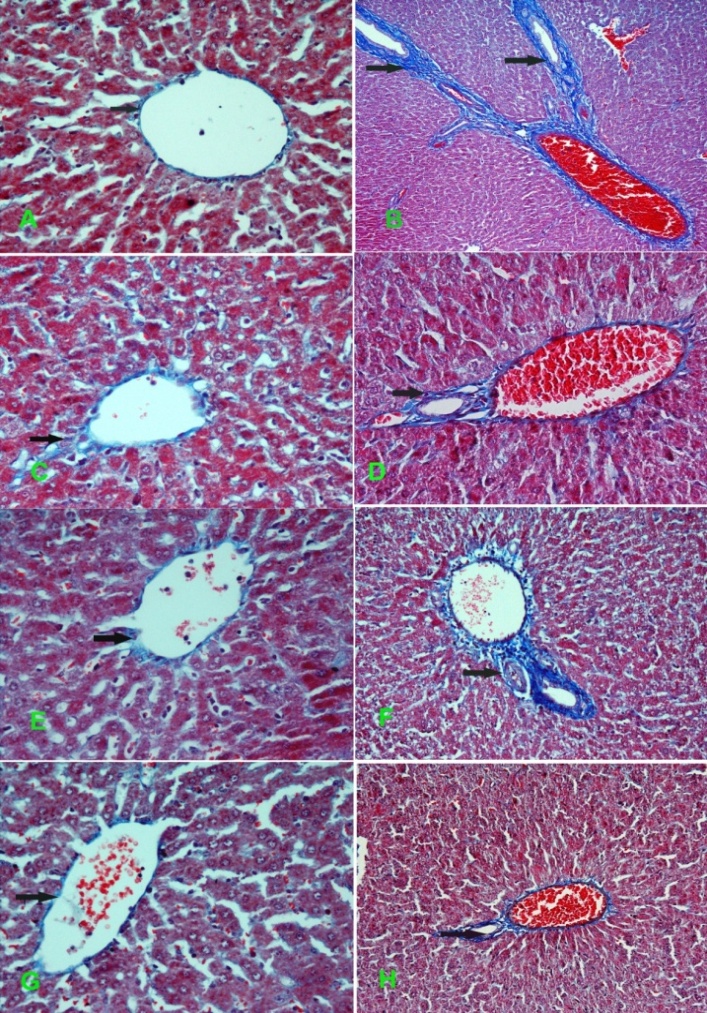

Plate 2: Histopathological examination of collagen deposition in liver tissues of rats by Masson’s trichome staining. Masson’s stain colors collagen green and hepatocytes red. The arrows indicate collagen deposition (400 X original magnification). Normal liver sections showed normal distribution of collagen (Plate 2A). LPS injection showed abundant pericentral collagen fibers fused together in dense bundles in liver tissues of rats (Plate 2B). WPI (100 mg/kg) showed mild collagen deposition and few connective tissue fibers compared to LPS (Plate 2C). WPI (200 mg/kg) showed slight pericentral collagen fibers in LPS-treated liver tissues (Plate 2D). α-LA (100 mg/kg) showed mild collagen deposition and fewer connective tissue fibers compared to LPS (Plate 2E). α-LA (200 mg/kg) showed moderate collagen deposition in LPS-treated liver tissues (Plate 2F). β-LG (100 mg/kg) showed mild collagen deposition and fewer connective tissue fibers compared to LPS (Plate 2G). β-LG (200 mg/kg) showed moderate collagen deposition in LPS-treated liver tissues (Plate 2H).

Examination of collagen deposition in liver tissues after induction of endotoxemia

Examination of normal liver sections showed normal distribution of collagen, which showed small amount of wavy fibrils (plate 2A). After LPS injection, abundant pericentral collagen fibers fused together in dense bundles were clearly visible after two weeks of endotoxemia. Also, trichrome staining demonstrated abundant bridging of collagen fibers (plate 2B). Ttreatment with WPI (100 mg/kg) showed improvement in collagen deposition and few connective tissue fibers as compared LPS (plate 2C). However, WPI at 200 mg/kg showed slight pericentral collagen fibers (plate 2D). On the other hand, α-LA (100 mg/kg) showed improvement in collagen deposition and connective tissue fibers as compared to LPS (plate 2E). However, α-LA (200 mg/kg) showed mild improvement in collagen deposition in endotoxic liver (plate 2F). Two-week treatment with β-LG (100 mg/kg) during endotoxemia showed remarkable improvement in collagen deposition and connective tissue fibers (plate 2G). However, β-LG (200 mg/kg) showed mild improvement in collagen deposition (plate 2H).